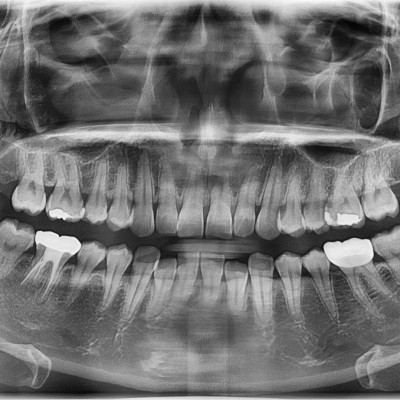

#28,38 사랑니 발치 #28,38 사랑니 발치 구강외과 전문의가 당일 발치했습니다.